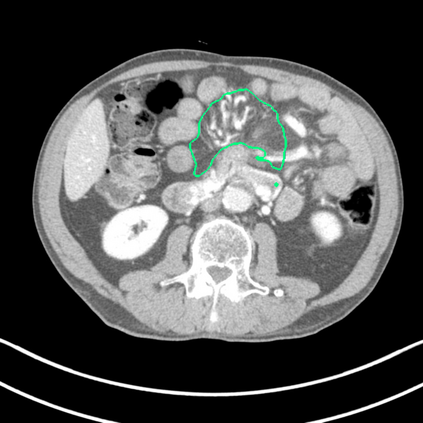

Radiomics uses quantitative medical imaging features to predict clinical outcomes. Currently, in a new clinical application, finding the optimal radiomics method out of the wide range of available options has to be done manually through a heuristic trial-and-error process. In this study we propose a framework for automatically optimizing the construction of radiomics workflows per application. To this end, we formulate radiomics as a modular workflow and include a large collection of common algorithms for each component. To optimize the workflow per application, we employ automated machine learning using a random search and ensembling. We evaluate our method in twelve different clinical applications, resulting in the following area under the curves: 1) liposarcoma (0.83); 2) desmoid-type fibromatosis (0.82); 3) primary liver tumors (0.80); 4) gastrointestinal stromal tumors (0.77); 5) colorectal liver metastases (0.61); 6) melanoma metastases (0.45); 7) hepatocellular carcinoma (0.75); 8) mesenteric fibrosis (0.80); 9) prostate cancer (0.72); 10) glioma (0.71); 11) Alzheimer's disease (0.87); and 12) head and neck cancer (0.84). We show that our framework has a competitive performance compared human experts, outperforms a radiomics baseline, and performs similar or superior to Bayesian optimization and more advanced ensemble approaches. Concluding, our method fully automatically optimizes the construction of radiomics workflows, thereby streamlining the search for radiomics biomarkers in new applications. To facilitate reproducibility and future research, we publicly release six datasets, the software implementation of our framework, and the code to reproduce this study.

翻译:放射科使用定量医学成像特征来预测临床结果。目前,在一个新的临床应用中,通过一个超常试验和高压过程,通过人工操作,从广泛的现有选项中找到最佳放射法。在本研究中,我们提议了一个框架,自动优化每个应用程序的放射工作流程的建设。为此,我们将放射作为模块工作流程,并包括每个部件的大量通用算法。为了优化每个应用程序的工作流程,我们使用随机搜索和聚合的自动机学习方法。我们用12种不同的临床应用来评估我们的方法,结果在曲线下应用的以下领域:1) 脂色瘤(0.83);2) 脱氧型纤维瘤(0.82);3 初级肝脏肿瘤(0.80);4 气肠肿瘤(0.77)、5 彩虹肝脏移植(0.61); 6 脑膜细胞变异常(0.45); 7) 肝细胞变异常(0.8) 脑纤维变异位(0.80); 9) 直径直线型癌症(0.74) 和头型癌症(0.77) 直径研究(10) 。